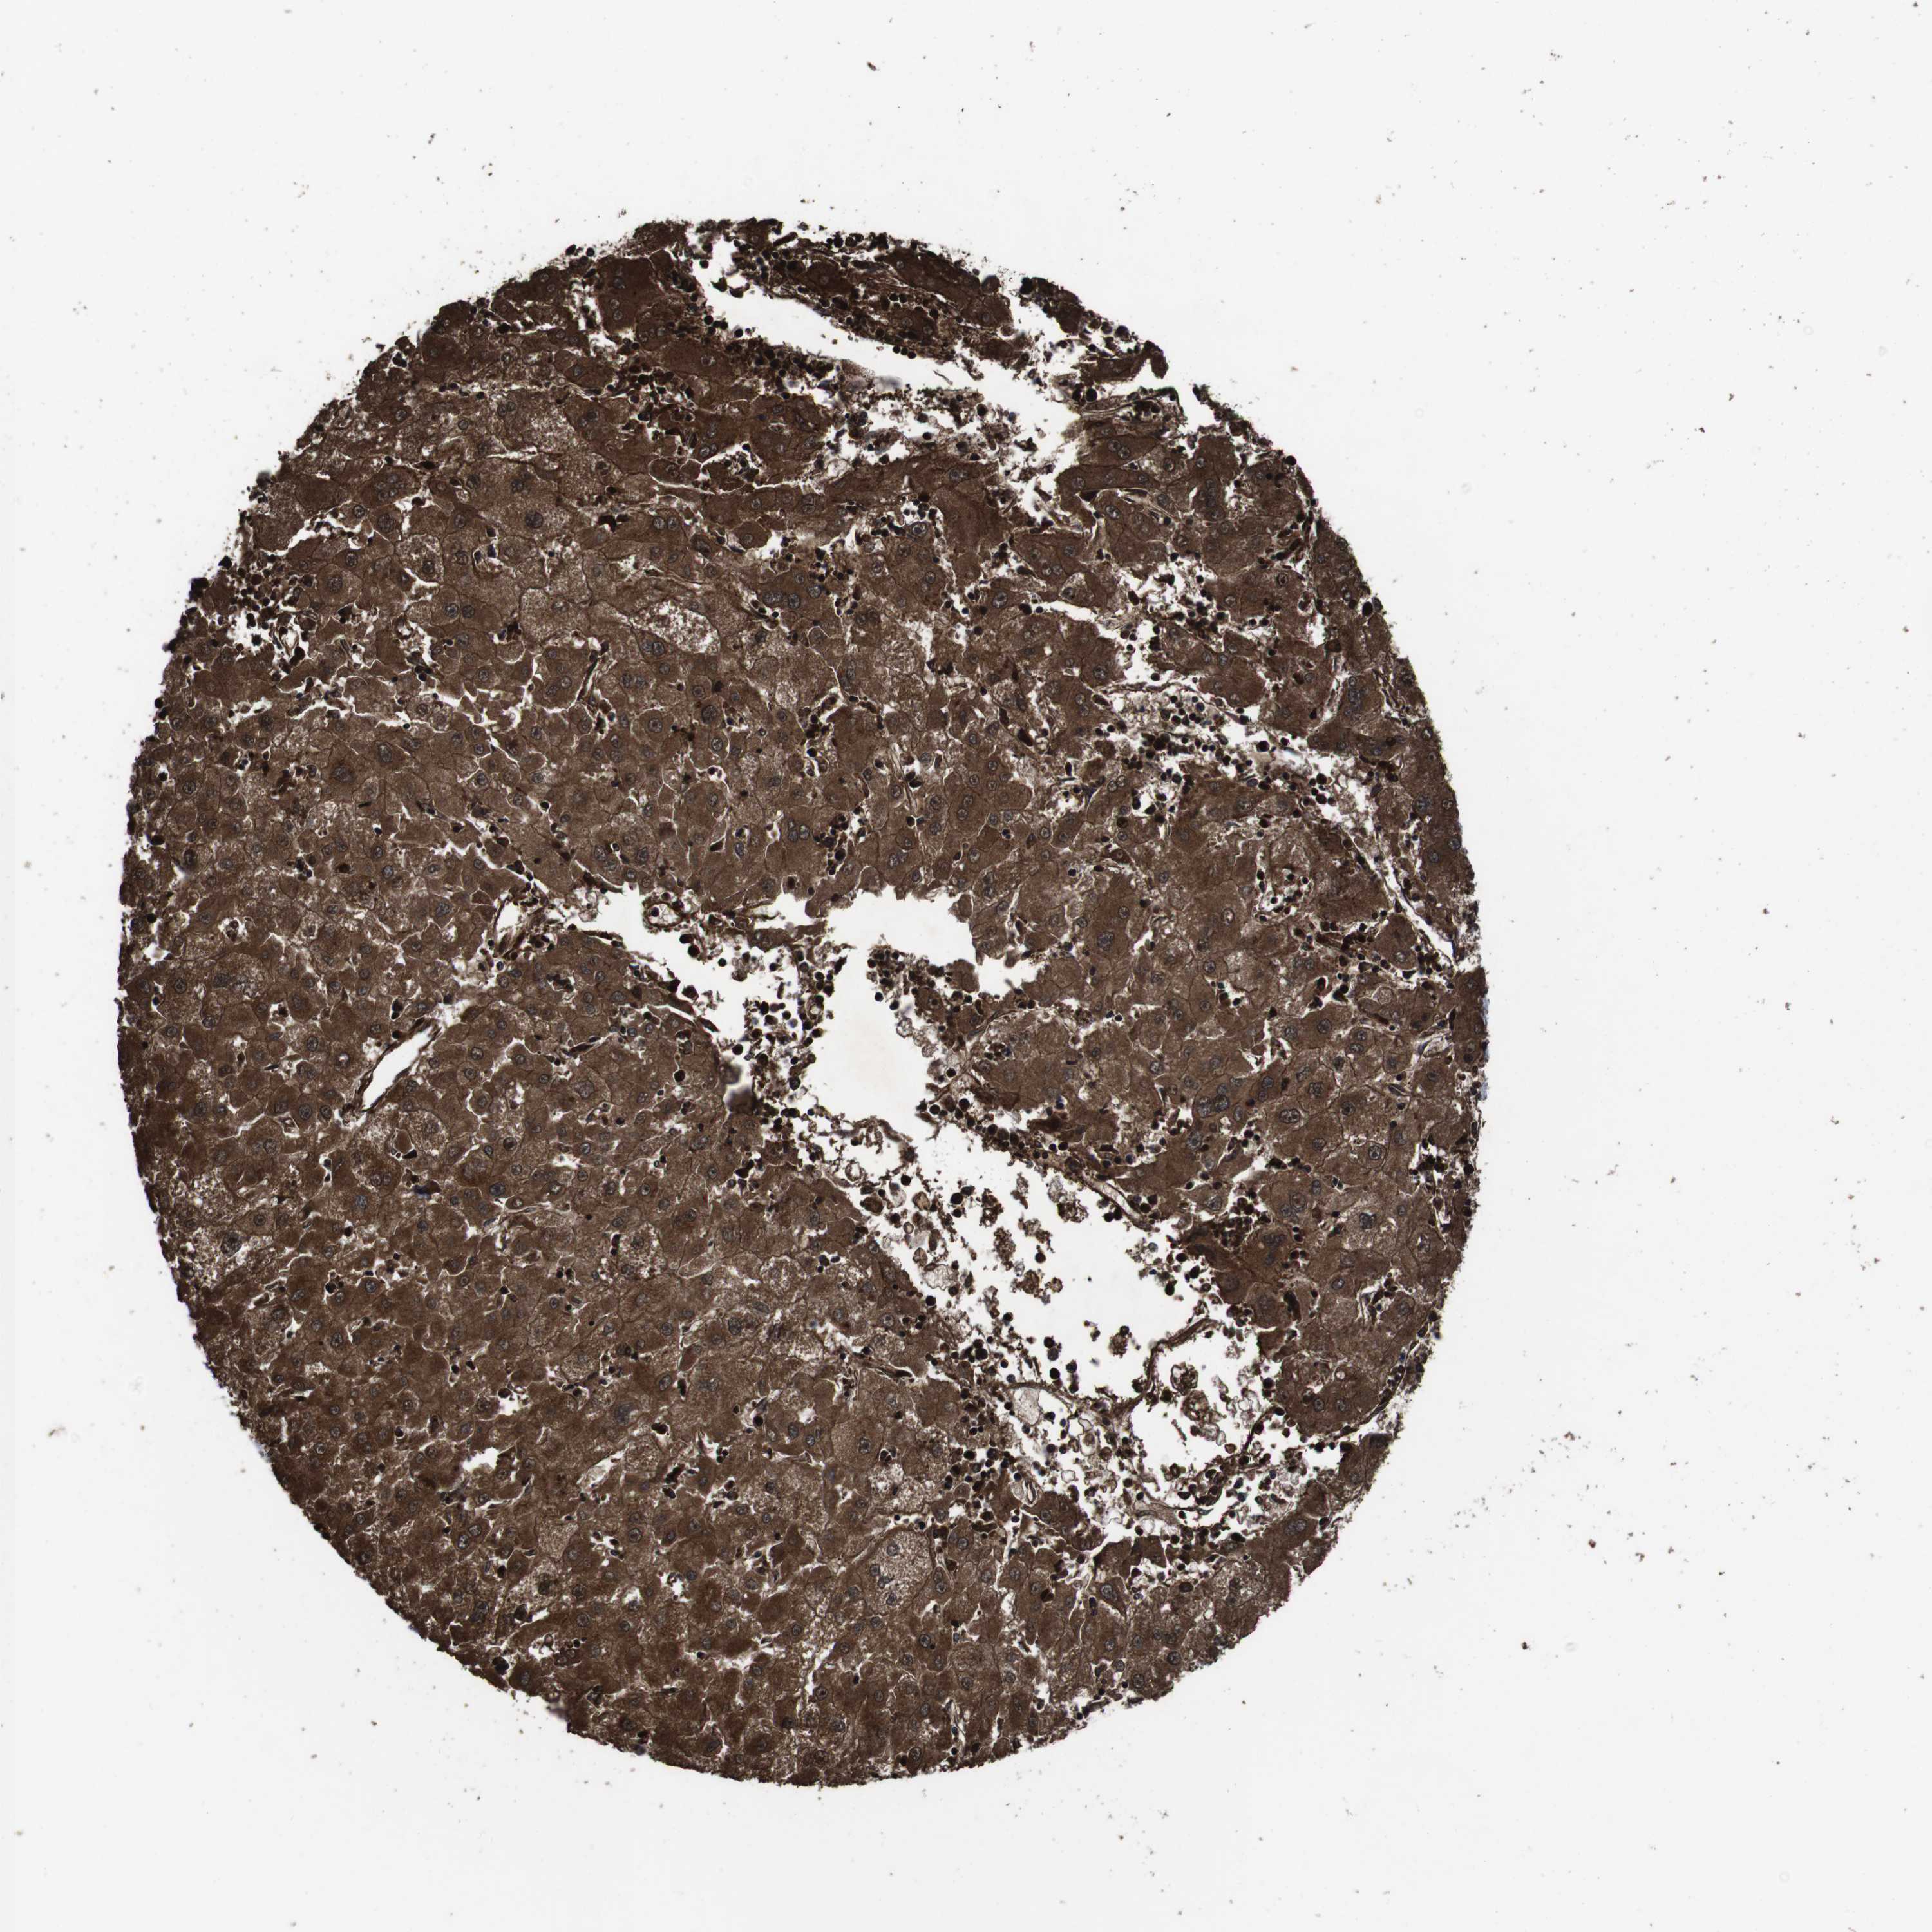

LIVER CANCER - Protein expressioni

A mouse-over function shows sample information and annotation data. Click on an image to view it in a full screen mode. Samples can be filtered based on level of antibody staining by selecting one or several of the following categories: high, medium, low and not detected. The assay and annotation is described here.

Note that samples used for immunohistochemistry by the Human Protein Atlas do not correspond to samples in the TCGA dataset.

Antibody stainingi

Antibody staining in the annotated cell types in the current human tissue is reported as not detected, low, medium, or high, based on conventional immunohistochemistry profiling in selected tissues. This score is based on the combination of the staining intensity and fraction of stained cells.

Each image is clickable and will lead to virtual microscopy that enables deeper exploration of all samples and also displays staining intensity scores, fraction scores and subcellular localization as well as patient and tissue information for each sample.

Antibody HPA045821

Antibody HPA054352

Antibody CAB012229

Staining

High

Medium

Low

Not detected

Intensity

Strong

Moderate

Weak

Negative

Quantity

>75%

75%-25%

<25%

None

Location

Nuclear

Cytoplasmic/membranous

Cytoplasmic/membranous,nuclear

Carcinoma, Hepatocellular, NOS

Cholangiocarcinoma